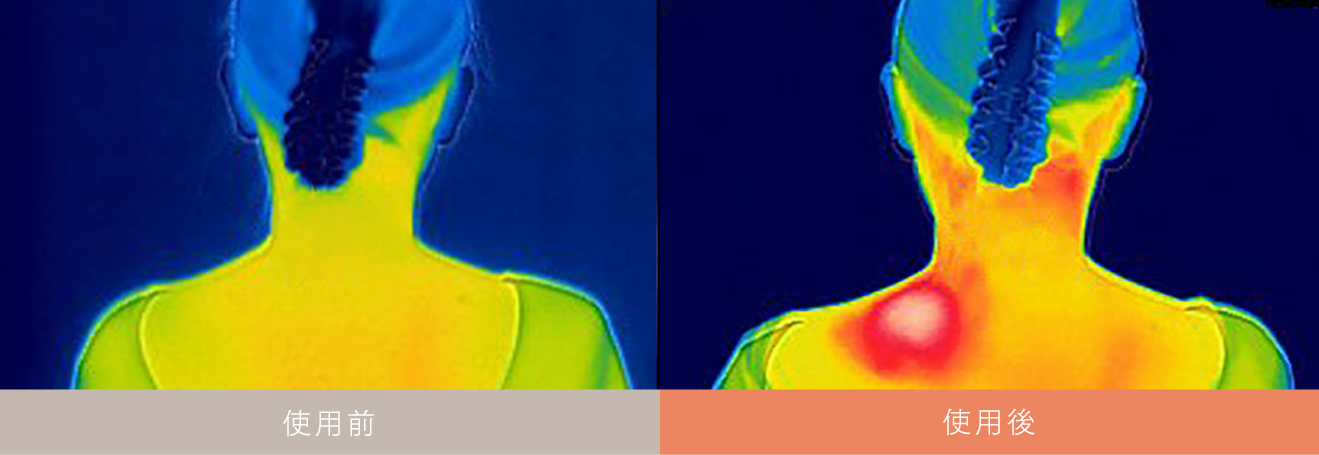

熱が深くまで届くから

いつもは届かないコリをピンポイント治療。

自重のチカラで刺激するから

深くまで熱が届く

熱が深くまで届くから

いつもは届かないコリへ

深くまで届く温熱効果で

気になる肩コリ・腰痛の

根本原因をピンポイントに治療

ONCUREPOINT1

「温熱」

温めながらほぐすから

筋肉の緊張を緩和。

冷えからくるコリや痛みにも

筋肉を暖めながらほぐすことで、筋肉痛や神経痛の痛みを和らげます。また冷えからくる、コリや痛みにも温熱がピンポイントに刺激し緩和します。